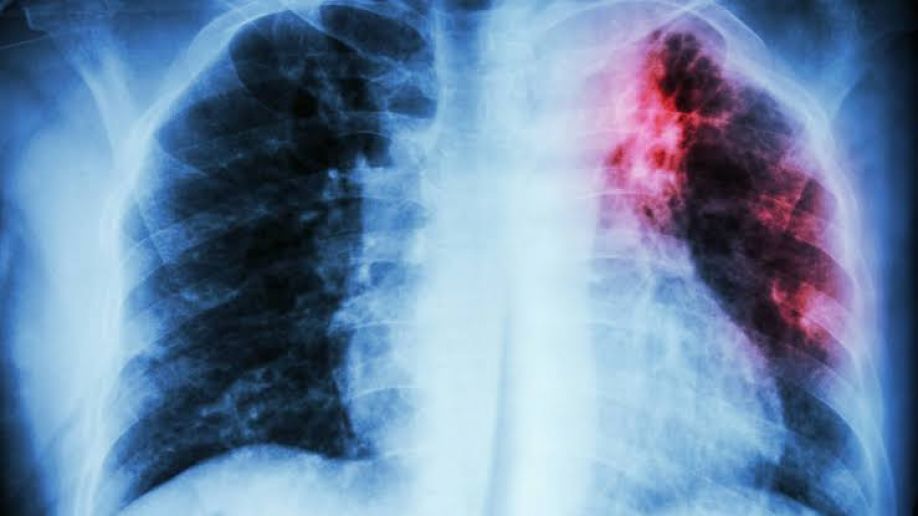

Expuso que el pulmón es un órgano cuyo tejido esponjoso permite el adecuado intercambio de oxígeno. “En la FPI, se genera un proceso anormal de cicatrización de este tejido que provoca disminución gradual e irreversible de la función pulmonar, causando dificultad para respirar, tos persistente, crepitaciones (sonido tipo velcro al exhalar aire), dolor torácico, acropaquia (engrosamiento de yemas y blanco de las uñas de los dedos que se curvan tomando el aspecto de palillos de tambor), fatiga y pérdida de peso, entre otros síntomas”.